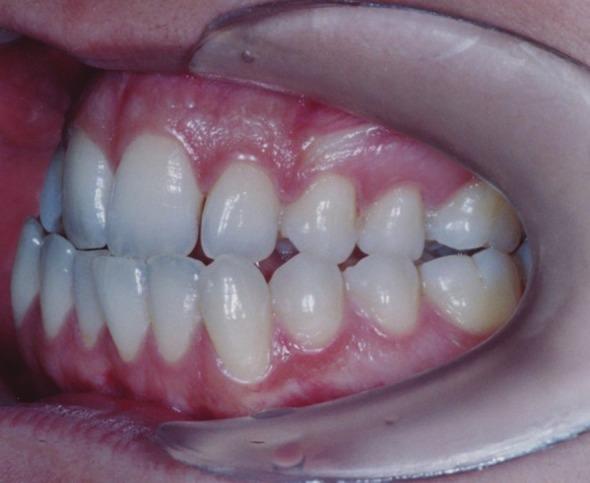

This case report presents a 22-year-old girl with class III malocclusion due to maxillary deficiency. The patient was referred for presurgical orthodontics; however, she rejected the surgery. This case was treated by means of Tongue appliance and slow palatal expansion, followed by lower fixed appliance, reverse chin cup, and upper fixed appliance. Tongue appliance and slow palatal expansion were used at the beginning of the treatment. After 6 months, reverse chin cup and lower fixed appliance were added. Six months later reverse chin cup was removed and upper fixed appliance was mounted. Positive overbite and over jet were achieved after 24 months of active treatment. Nasolabial angle also showed improvement. Nonsurgical treatment of adult class III patients is a difficult procedure; however, this patient was treated nonsurgically.

本病例报告介绍了一名22岁因上颌骨发育不足导致III类错牙合畸形的女孩。该患者被转诊接受术前正畸治疗;然而,她拒绝了手术。本病例采用舌弓矫治器和慢速腭扩展进行治疗,随后使用下颌固定矫治器、反向颏兜和上颌固定矫治器。治疗开始时使用舌弓矫治器和慢速腭扩展。6个月后,增加了反向颏兜和下颌固定矫治器。6个月后,移除反向颏兜并安装上颌固定矫治器。经过24个月的积极治疗,实现了覆牙合和覆盖正常。鼻唇角也有所改善。成年III类患者的非手术治疗是一个困难的过程;然而,该患者接受了非手术治疗。